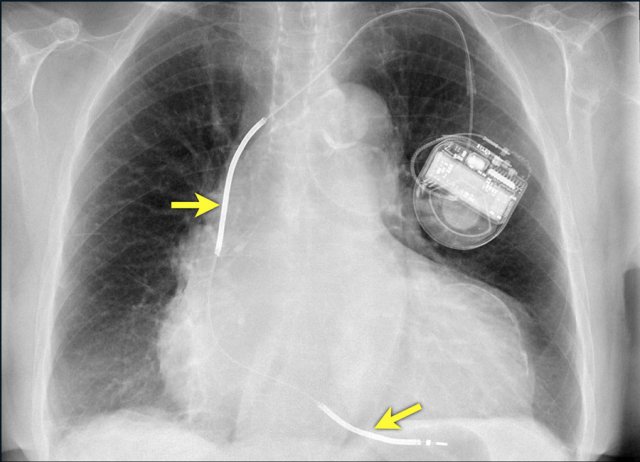

Here a biventricular pacemaker with three leads.

The right atrial pacemaker lead is located in the atrial appendage.

This lead first travels inferiorly into the right atrium and then turns upward and anteriorly where it is anchored within the trabeculae of the atrial appendage.

The left ventricular lead travels through the right atrium and the sinus coronarius and is finally positioned posteriorly into a cardiac vein on the left.